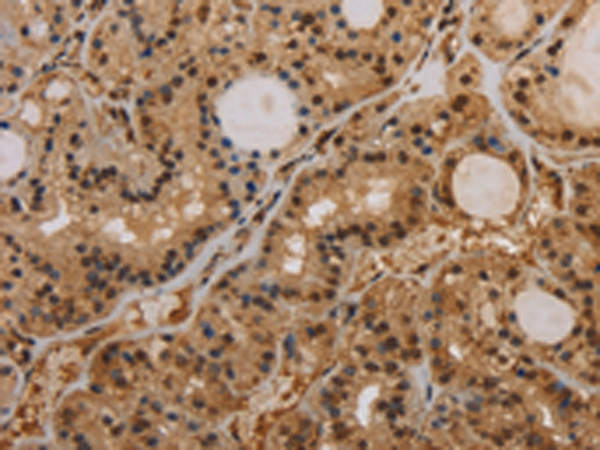

分类: 科研抗体货号: P05052别名: HIP; PAP; PAP1; REG3; INGAP; PAP-H; PBCGF; HIP/PAP; REG-III应用: WB,IHC反应种属: Human